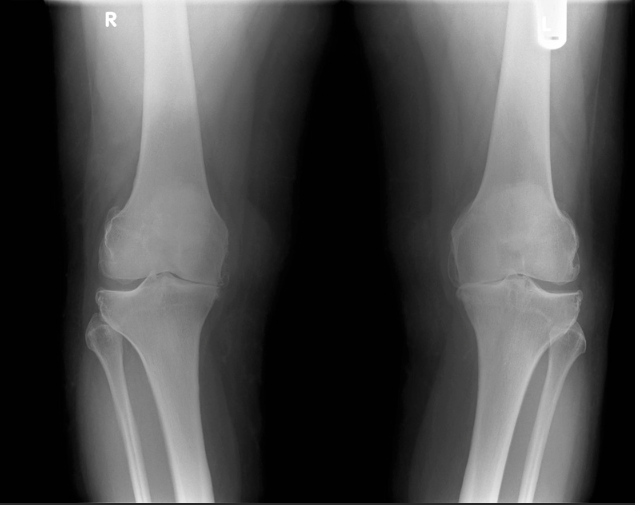

무릎 통증

이런 증상이 있다면?

계단 오르내릴 때 무릎 통증

무릎이 붓고, 가만히 있어도 아픔

오다리, 평발로 인한 반복적 무릎 손상

노화 외에도 평발, 오다리 같은 체형 문제로 인해 무릎관절이 손상되기도 합니다.

스포츠 손상도 무시할 수 없고요.

진료를 보면 50~60대 무릎 통증 환자 중 상당수가 평발이나 오다리를 가지고 있는 경우가 많습니다.

어떤 치료가 효과적일까요?

히알루론산, PRP, 줄기세포주사 등 다양한 무릎 주사치료

운동치료로 무릎 관절 안정화

봉약침으로 염증 완화

추나요법으로 무릎 정렬 개선

오다리, 평발 교정도 병행 필요